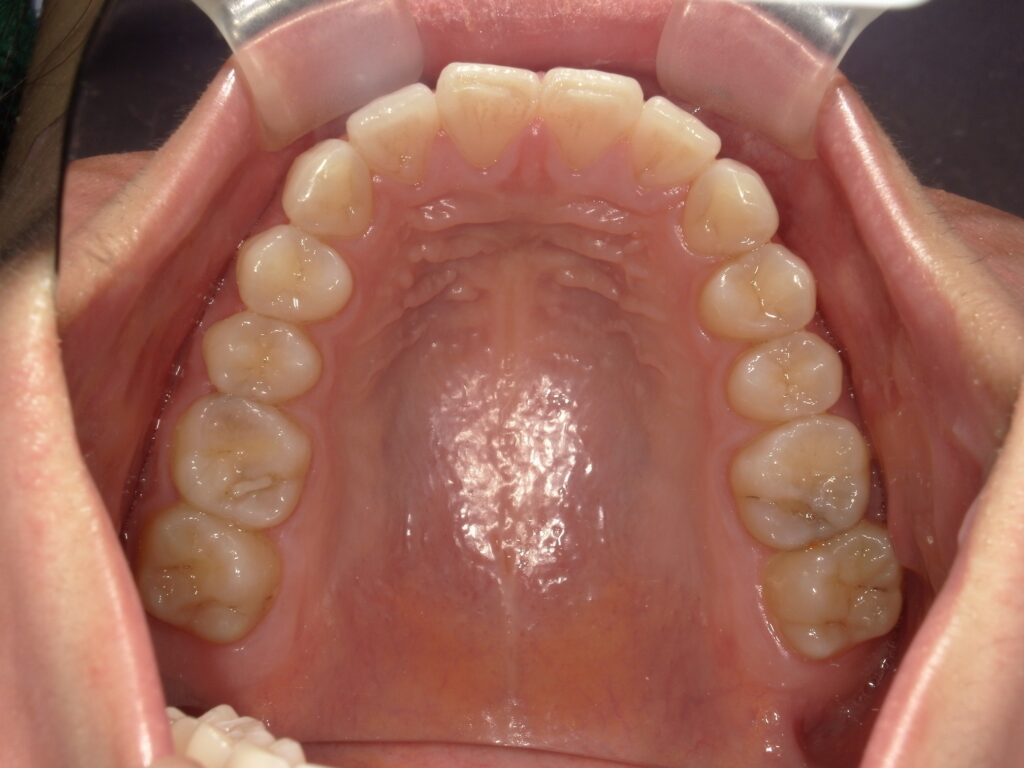

After

部分矯正とは、気になる一部分だけを動かす矯正治療です。

特に多いのが「上の前歯だけ」「下の前歯だけ」というケースです。